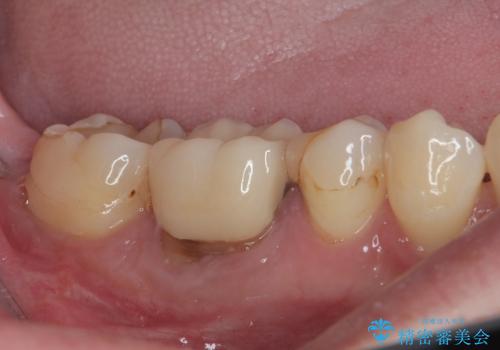

割れて揺れている奥歯 抜歯即時・早期埋入インプラント治療